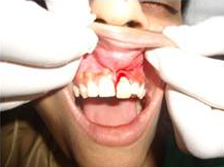

Drilled socket for Implant

Single Tooth Implant